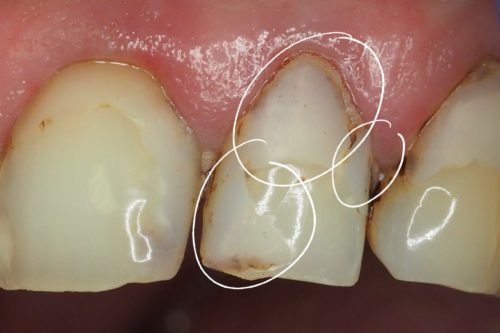

Pacjentka zgłosiła się z powodu licznych, nieszczelnych i nieestetycznych wypełnień w górnej dwójce

Usunięto stare wypełnienia, opracowano ubytki i wykonano estetyczną odbudowę korony zęba materiałem kompozytowym